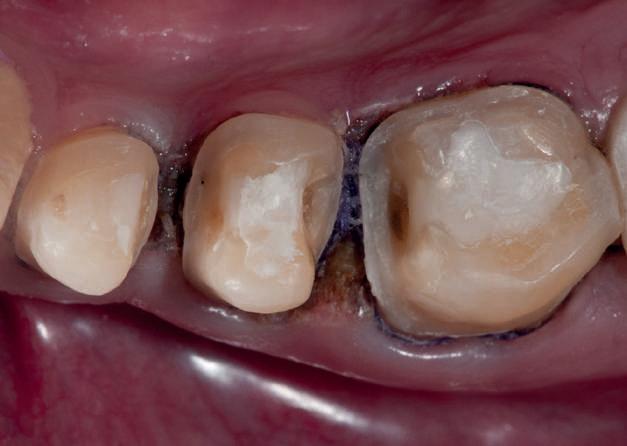

HYBRID COMBINATION RESTAURATIONS

Vonlay-uri: o alternativă conservatoare estetică la coroanele cu acoperire totală